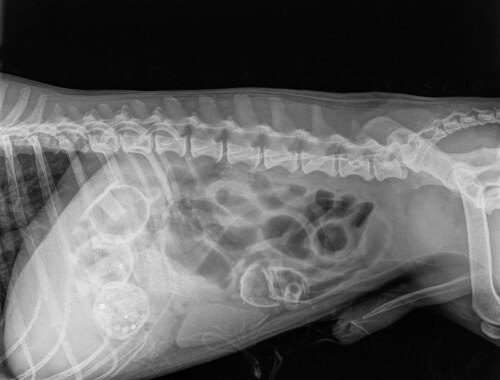

También, las imágenes abdominales obtenidas por ultrasonidos o rayos X, pueden revelar cualquier cuerpo extraño. Si el objeto no se desplaza dentro del intestino, el perro puede necesitar cirugía bajo anestesia para que el veterinario pueda abrir el abdomen y eliminar la causa del bloqueo.